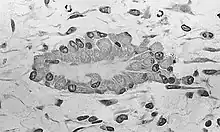

En esta etapa de desarrollo, se producen más cambios en la morfología de las células osteoprogenitoras: su forma se vuelve más columnar; la cantidad de aparato de Golgi y retículo endoplásmico en bruto aumenta, y las células comienzan a crear una matriz extracelular que consiste de fibrillas de colágeno tipo I. Esta matriz es osteoide y las células que lo crearon son osteoblastos. Mientras que los osteoblastos recubren la periferia del nódulo, siguen formando osteoide en su centro y algunos de ellos se incorporan dentro de ella para convertirse en osteocitos.[3]

En este punto, el osteoide se mineraliza resultando en un nido formado por osteoide mineralizado que contiene osteocitos y está bordeada por los osteoblastos activos. El nido, que comenzó como un conjunto difuso de CMM, se ha convertido en tejido óseo rudimentario.[3]